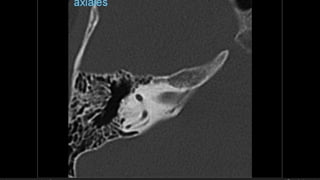

Evaluación Imagenologica

• #38 Izqu. AXIAL-- fxLongitudinal perdonan la capsula otica (laberinto oseo) Centro AXIAL fx trnasversa lascuales tperdonan el lab erinto oseo Dere: MIXTA – tmp perdona

• #48 cochlear aqueduct, vestibular aqueduct Gs Sulcum glosofaríngeo Jf foramen yugular